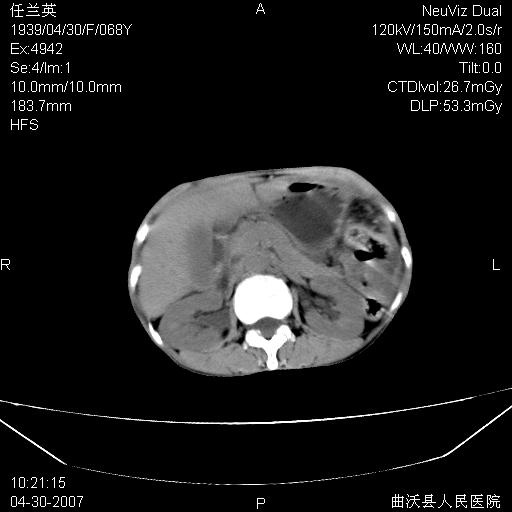

患者,女,68岁,感觉腹部憋涨发硬数天,查b超发现左盆腔有囊性肿物和少量腹水,行ct检查

1.考虑卵巢肿瘤并腹腔广泛性转移可能性大;

2.腹盆腔少量积液。